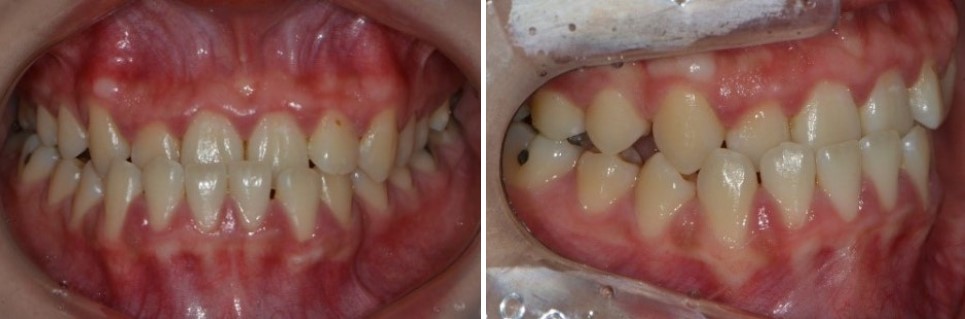

케이스 1. 앞니·어금니가 모두 거꾸로 물렸던 주걱턱, 수술 없이 교정으로

먼저, 비수술 교정으로 치료를 잘 마친 환자분의 치료 전 상태를 보겠습니다.

원칙적으로 이상적인 앞니 교합은

윗니가 아랫니보다 살짝 앞으로 나와

아랫니를 부드럽게 덮어주는 형태입니다.

어금니 역시

윗니가 아랫니보다 약간 바깥쪽에 위치하면서

아랫니를 안정적으로 감싸는 모습이 이상적입니다.

하지만 이 환자분의 경우에는,

앞니와 어금니가 모두 거꾸로 물리는 반대교합 상태였습니다.